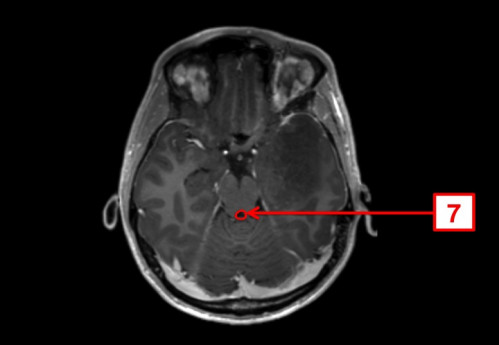

ICD: C71.9

23-jähriger Mann. Bereits seit Jahren plagen ihn Kopfschmerzen, die vor allem bei körperlicher Belastung auftreten. In den letzten Tagen fühlte er sich zunehmend unwohl, die Kopfschmerzen sind nun auch in Ruhe vorhanden.

Seit gestern Abend erbricht er sich mehrmals, und spricht, als ob er betrunken wäre.